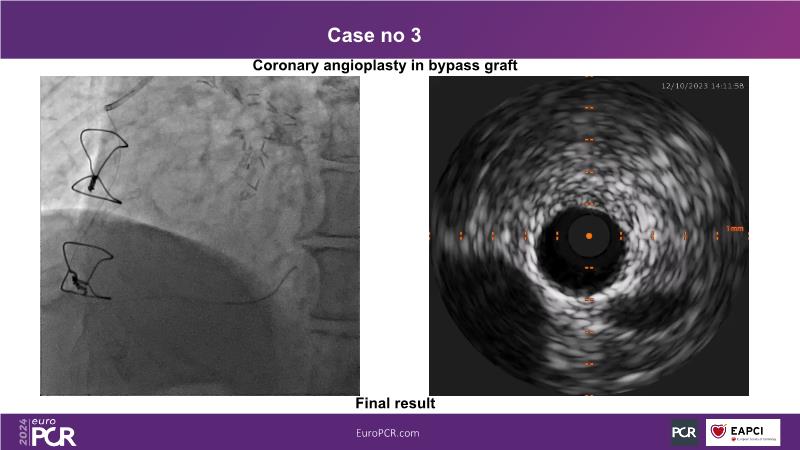

In this session, discover the effectiveness and safety of robotic PCI for both simple and complex lesions requiring additional devices like IVL, IVUS, laser, and FFR. Learn about the numerous benefits of robotics for patients and cathlab teams, including enhanced precision in wire navigation and stent positioning, full radioprotection, and reduced orthopedic injuries. Explore the growing interest in robotics within the interventional cardiology community, anticipate future technical advancements, and understand how AI will accelerate the integration of robotics and vice versa.